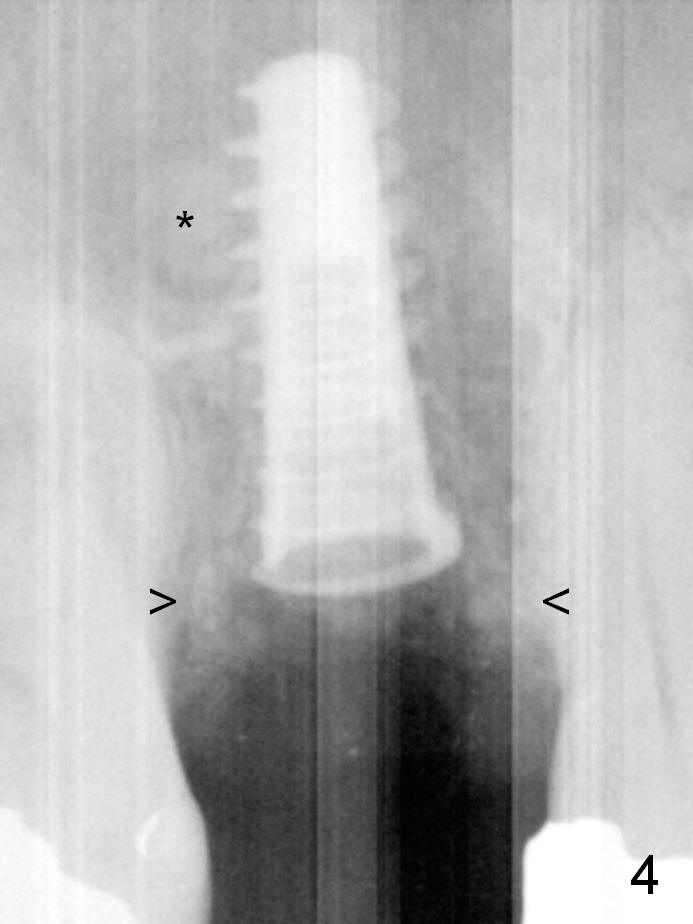

To prevent sinus lift related sinusitis, a shorter implant is going to be placed (Fig.1), approximately 2 mm beyond the apex.  Following extraction, the buccal plate (Fig.3a (coronal section): B) is not only ~ 2 mm shorter than the palatal one (P), but also thinner.  Since the bone density of the palatal plate is higher, without osteotomy an implant is less likely placed in the middle of the socket (S (Fig.1); Fig.3b) than buccal (Fig.3c).  Therefore drills are used to form osteotomy in the apical 1/3 of the palatal slope (Fig.3d (red arrow); SM: sinus membrane).  When 3.3 mm Magic Drill (MD) is in place (Fig.2), the distal surface of the sinus septum is perforated without air leakage.  Demineralized allograft (.0125-.085) is placed for sinus lift (Fig.4 *) prior to placement of 4.5x11 mm implant with ~ 30 Ncm.  The implant is slightly buccal to the ideal position indicated in Fig.3e (curved blue line: sinus lift).  A 4.5x4(2) mm pair abutment is placed for an immediate provisional to hold mineralized allograft in the remaining socket gaps (Fig.4 arrowheads, .5-1.5 mm).  A 9 mm implant may avoid sinus floor perforation on the distal slope of the 2nd premolar.  The osteotomy should have been established initially as mesial as possible.  In fact the patient has nasal hemorrhage while sneezing for the first 2 days postop.  Although he complains of pain buccal to the implant, the gingiva appears to heal 7 days postop (Fig.5).  The distobuccal papilla appears to be displaced somewhat.  Raising mucoperiosteal flap is most likely associated with postop pain and esthetic compromise.  The implant appears to have osteointegrated 5 months postop (Fig.6).  A 4.5 mmx15° 3 mm cuff angled abutment is placed for final restoration.  The distolingual portion of the implant is supported by the regenerated bone 3 years post cementation (Fig.7,8).  There is no bone loss 4 years 2 months post cementation (Fig.9,10).